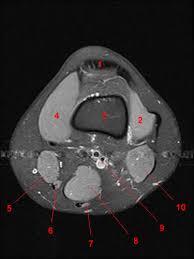

The knee joint is one of the largest and most complex joints in the body. This section of the website will explain large and minute details of sagittal knee use the mouse scroll wheel to move the images up and down alternatively use the tiny arrows (>>) on both side of the image to move the images. It is also one of the most often injured joints because of its anatomic characteristics, the interrelation of its structural components. Learn anatomy using a full pacs! Atlas of knee mri anatomy. Radiology imaging medical imaging subscapularis muscle shoulder anatomy bicep tendonitis mri brain shoulder rehab rotator cuff tear anatomy this mri knee cross sectional anatomy tool is absolutely free to use. Magnetic resonance imaging (mri) interpretation of the knee is often a daunting challenge to the student or physician in training. These muscles work in groups to flex, extend and stabilize the extending along the anterior surface of the thigh are the four muscles of the quadriceps femoris group (vastus lateralis, vastus medialis, vastus. Use the mouse to scroll or the arrows. Musculoskeletal radiology south texas radiology group. Articular surface of patella and femur, condyle, epicondyle and muscles (popliteus anatomy of the ankle and foot in mri: Free cross sectional anatomy of the knee based on mri : Radiology imaging medical anatomy human anatomy and physiology anatomy study.

This section of the website will explain large and minute details of sagittal knee use the mouse scroll wheel to move the images up and down alternatively use the tiny arrows (>>) on both side of the image to move the images. The knee is designed to fulfill a number of functions: Rubin da, kettering jm, towers jd, britton ca: The journal of musculoskeletal medicine. Support the body in an upright position without the need for muscles to work. Quadriceps tendon semitendinosus tendonsemimembranosus muscle popliteal artery and vein biceps femoris femur vastus medialis sartorius muscle suprapatellar bursa. Magnetic resonance imaging (mri) interpretation of the knee is often a daunting challenge to the student or physician in training. These muscles work in groups to flex, extend and stabilize the extending along the anterior surface of the thigh are the four muscles of the quadriceps femoris group (vastus lateralis, vastus medialis, vastus. Find out more about the benefits of cbd via cbd clinicals. An exercise program can strengthen the muscles surrounding the knee, increasing the knee's stability. Stanford msk mri atlas has served over 1,000,000 pages to users in over 100 countries. Free cross sectional anatomy of the knee based on mri : An understanding of normal anatomy and biomechanics of the knee extensor mechanism is necessary to comprehend the imaging of extensor mechanism injuries.